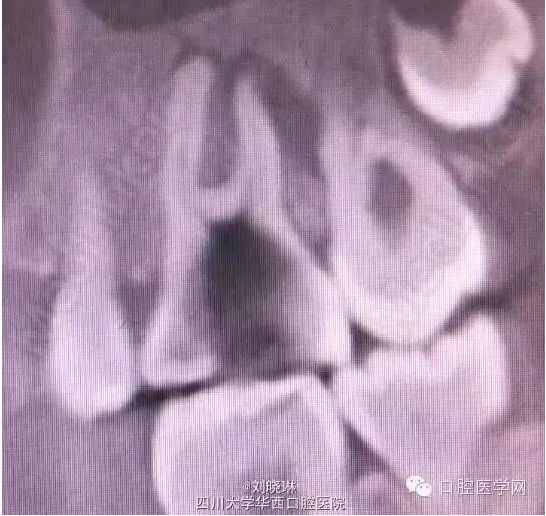

CBCT示:16牙合面大面積牙體組織密度減低影,與髓腔穿通,腭側根管內可見高密度影像,超出根尖孔外至上頜竇,根尖周組織暗影。